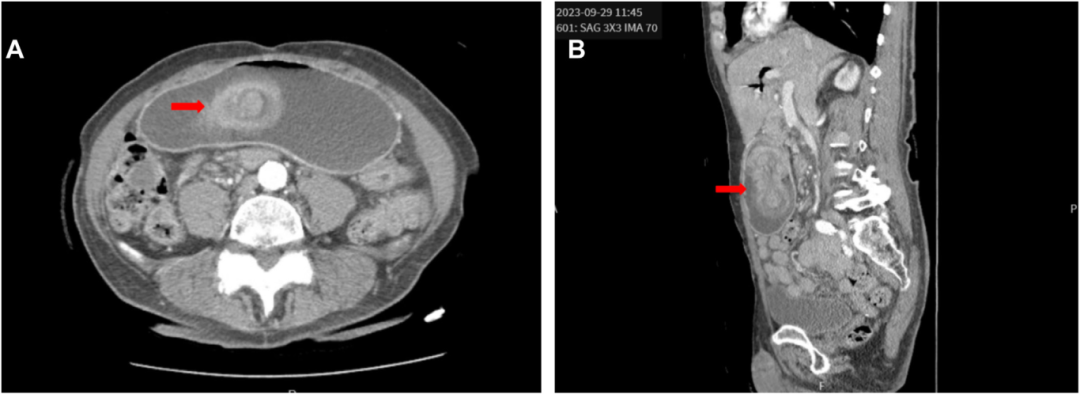

“靶环”警报!76岁老人Whipple术后突发腹痛呕吐,影像学揪出元凶

病例简介患者,男性,76 岁。主诉:因急性上腹痛、腹胀伴有呕吐和便秘3天,到急诊科就诊。关键病史:既往有胰腺癌病史,曾接受过胰十二指肠切除术(Whipple 手术)。查体示:腹部检查显示弥漫性压痛,无肌紧张。影像学发现:床旁超声(图 1)。计算机断层扫描(CT)(图2)。图 1 上腹部床旁超声图 2 CT成像显示(A)横断面和(B)矢状面你的诊断是什么?后续如何干预?(评论区说说你的看法)